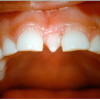

Sügav hambumus või sügav kattumine eesmiste hammaste osas

Normaalse hambumuse puhul katavad ülemised eeshambad alumisi 1/3 krooni pikkuse ulatuses ning alumiste eeshammaste lõikeserv on kontaktis ülemiste lõikehammaste suulaepoolse pinnaga. Sügavhambumuse puhul katavad aga ülemised hambad alumisi lõikehambaid rohkem...